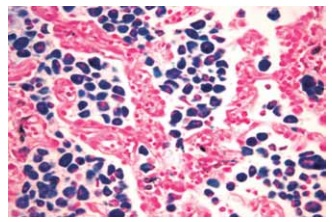

Paciente masculino, 52 anos, hipertenso e tabagista, deu entrada em um Pronto-Socorro Hospitalar, na região leste de São Paulo, com dificuldade de respirar e muito cansaço. Relatou que foi tratado há 20 dias de uma pneumonia e que fez corticoterapia de 07 dias. Todavia, não apresentando melhoras, este retornou à unidade.

Foi solicitada uma tomografia, que demonstrou opacidades em vidro despolido com predomínio nas bases e periferia do parênquima pulmonar. Os exames laboratoriais não acusaram patógeno viral ou bacteriano, e o paciente foi submetido a um exame de biópsia pulmonar. A amostra cirúrgica foi recebida previamente fixada em formol tamponado a 4% e submetida ao processamento da análise com inclusão total do material. As secções obtidas foram coradas utilizando hematoxilina e eosina.

Enunciado 4449126-1 Legenda: Espessamento de septos com infiltrado inflamatório.

Enunciado 4449126-2 Legenda: Macrófagos com ferro.

(Laboratório de Anatomia Patológica do Centro Universitário FMABC. Imagem usada com autorização)

O diagnóstico de DIP (pneumonia intersticial descamativa) foi feito correspondendo à clínica de pulmão do tabaco. O parênquima pulmonar demonstra presença de macrófagos intra-alveolares, multinucleados e com pigmento granular castanho contendo ferro, que é demonstrado pela técnica